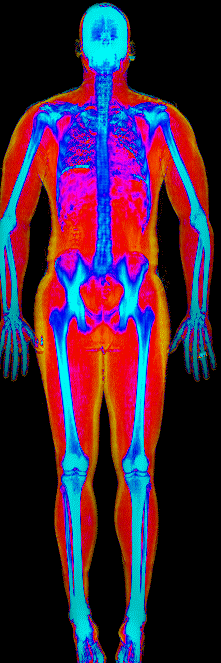

What Fat Loss Looks Like on a DEXA Scan

Red = muscle, gold = fat, blue = bone.

Lost 26.0 lb of fat · 187 → 150 lb · Age 44

Lost 25.4 lb of fat, gained 3.7 lb lean · 201 → 180 lb · Age 33

Lost 24.9 lb of fat, gained 12.0 lb lean · 183 → 170 lb · Age 37